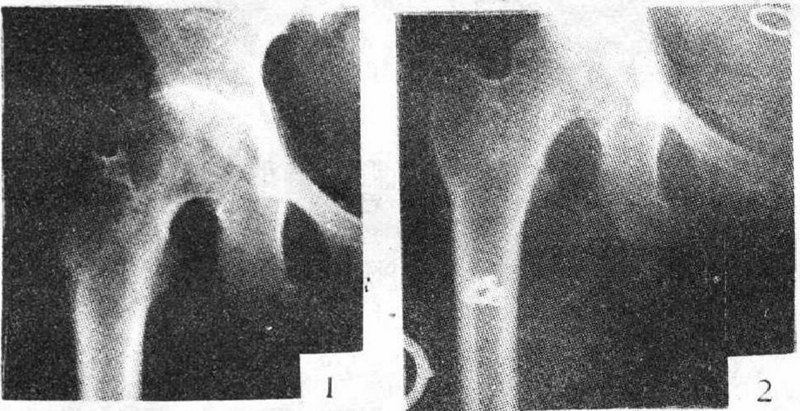

髓芯减压联合非血管化骨移植术最早由Phemister在1930年报道,骨移植给股骨头坏死区域提供了结构支撑或者起到支架作用促进骨重建。最常见的是通过髓芯减压通道植入,还有trap door technique 和light bulb procedure技术。

非血管化骨移植考虑到减少供区的发病率以及较少的技术要求更受临床欢迎。目前,供区分离骨移植模式很少单独使用,一项长达14年的随访研究发现,非血管化骨移植治疗临床效果较差。需要技术改进结合生长因子或者骨移植替代物进行骨重建。国内学者应用髓芯减压联合打压植骨术治疗ARCO Ⅱ、Ⅲ型股骨头坏死,平均随访24个月,结果股骨头存活率达81%,平均HSS评分由术前61增加到86。

优点:①死骨的祛除不仅刺激新骨形成,而且为新骨的爬行替代奠定了基础;②隧道的建立可有效释放股骨头内高压;③减压处血管的重建改善了股骨头局部血液流变学状态;④植骨增强了减压区的力学稳定性及支撑作用;⑤减压植骨加固了死骨和新骨之间的断裂带,增加了股骨头内环境的稳定性;⑥操作简易,便于推广。

缺点:①死骨清除不彻底;②手术创伤不可避免;③对塌陷后中晚期的ONFH疗效不佳;④术后卧床时间长等